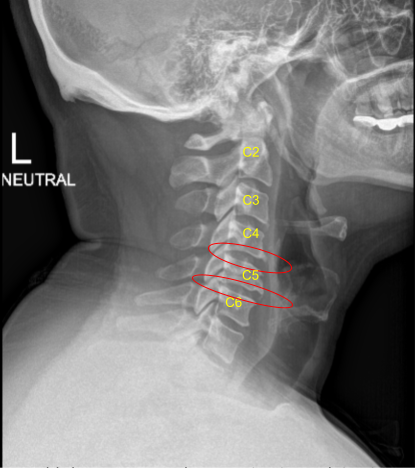

A pleasant patient who was involved in a car crash and subsequently developed neck pain. They had lots of conservative treatments, but ultimately failed, and developed myelopathy with correlated imaging findings from C4 to C6. Therefore, we offered surgery. The patient gave informed consent, understanding all of the risks, benefits, and alternatives to surgery.

Mild degenerative changes C4-C5 and C5-C6